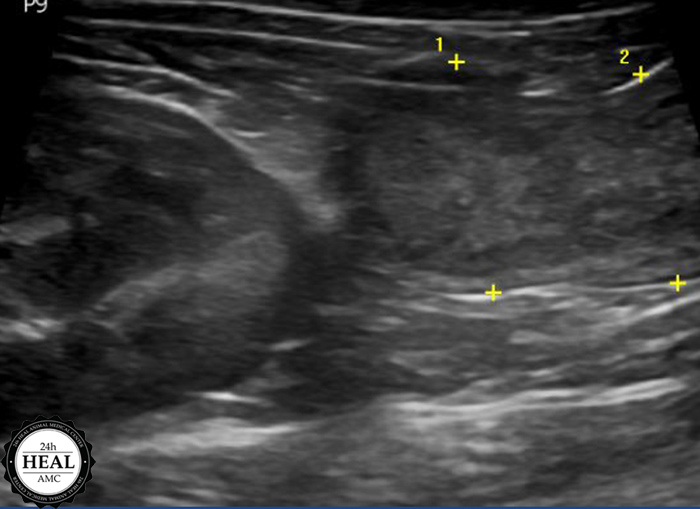

정확한 원인을 파악하기 위해 방사선, 초음파 검사를 실시했습니다.

초음파 검사 결과 미*는 자궁 내 농성이물이 의심되는 소견이 있었습니다.

추가적으로는 구토, 설사, 체중 감소, 복압 항진 등이 있습니다.고양이 자궁축농증 진단 초음파를 통해 가장 정확한 진단이 가능하며, 추가적으로는 혈액검사, 소변검사 등이 필요하였습니다.